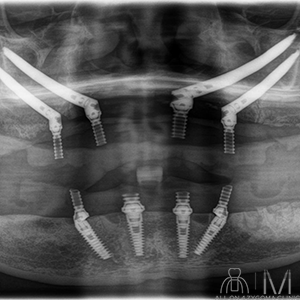

術後パノラマ画像所見

4本のザイゴマインプラントと4本のノーマルインプラントに8本のアバットメントを認める。上下とも最終補綴物を示唆する所見を認める。